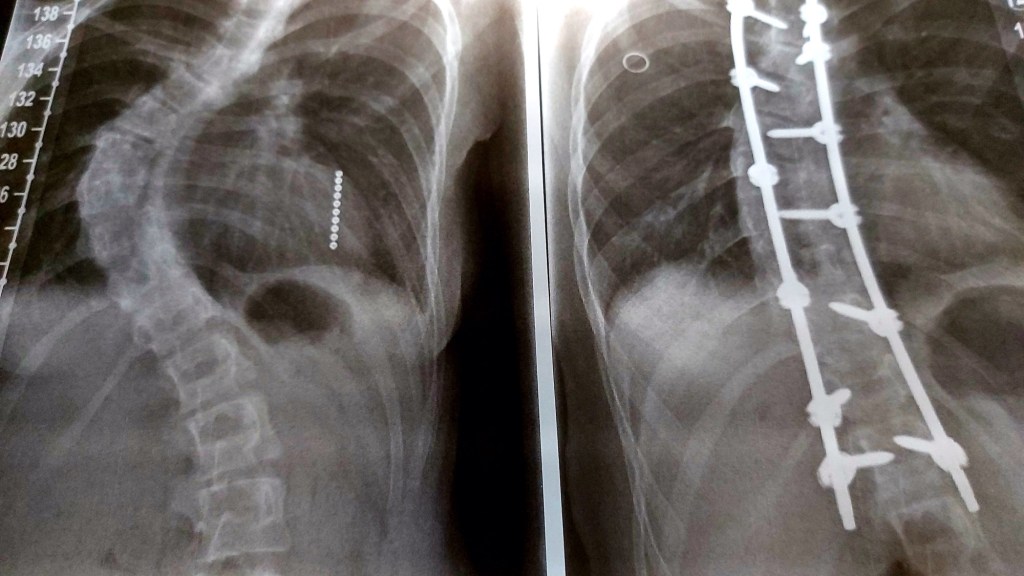

Vandaag zag ik een programma over een scoliose operatie van een dame van 16 jaar. Ik schrok daar een beetje van.

Eva was 12 toen haar die operatie aangeboden werd. Voor mijn gevoel te vroeg. Zij is nog steeds mega scheef. Komt nooit meer goed. Een puber leeft elke dag met dit gebeuren. Hadden wij niet beter kunnen wachten…. lastig lastig.

Het is wat het is. Eva heeft een litteken van nek tot bil. Best wel stoer.

Haar rug? Staat zeker niet recht. Best wel heftig scheef. Daar is nu niks meer aan te doen. Ik heb best wel met Eef te doen. Al die beperkingen. Maar mevrouw gaat ervoor. Ik geef eerlijk toe; met ups and downs. De downs zijn ook echt wel vaak aanwezig.